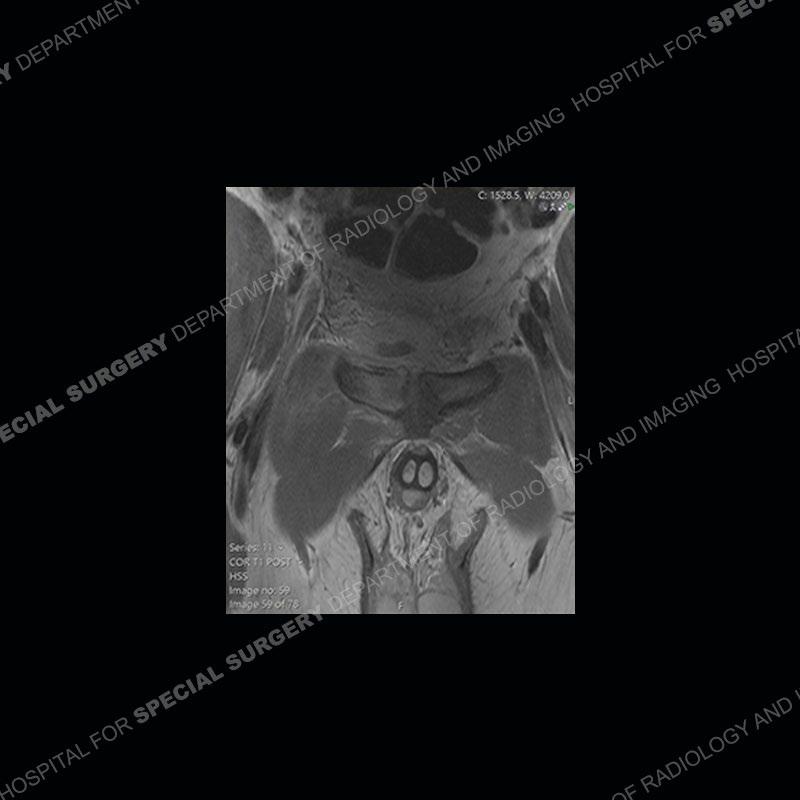

Radiographs did not demonstrate any clear abnormality. The MRI shows markedly abnormal signal of the right superior pubic ramus and abnormal signal/”mass” extending into the adjacent soft tissue. The inferior articular surface of the ramus showed what was thought to be bony destruction. CT examination shows a destructive process of the right superior pubic ramus.

Subsequent MRI in a very short time interval shows markedly increased abnormality of the ramus and increased edema and “mass” of the soft tissue. Post contrast imaging shows multiple, rim enhancing collections of the soft tissue and similar albeit less conspicuous enhancing collection of the ramus.

This case was a bit surprising to all involved given that the young man is otherwise in good health and extremely active in sports. The original thought was this case was going to be an overuse injury or stress fracture. The pubic ramus with the adjacent physis acts as a metaphyseal equivalent and although not frequently thought of would be a reasonable location for infection/osteomyelitis. The first MRI was somewhat confusing as the process did not have an appearance of a stress injury or rectus adductor aponeurosis injury. The degree of edema of the bone and soft tissue together would be odd especially for a sports hernia process. Initially, the thought was of an aggressive process which could be infection or neoplastic. Particularly, the abnormal architecture of the inferior surface of the ramus looked like a destructive process.